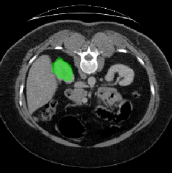

Figure 3 illustrates the specific segmentation results on the SABS dataset under Setting 1. Our model demonstrates higher accuracy in segmentation and effectively reduces unnecessary segmentation. Even under Setting 2, where the test class is entirely invisible to the model, our model performs well, as depicted in Figure 4. Given that SABS is a multi-organ dataset with many organs of small size, precise segmentation proves challenging. However, our model excels, particularly in the scenario of completely invisible classes, which closely resembles real-world conditions. Figure 4 highlights our model’s ability to accurately segment very small target organs, such as the right kidney. In contrast, the ADNet method fails to produce effective segmentation predictions, and other methods exhibit varying degrees of over-segmentation. On the CMR dataset, as shown in Table 2, our model generally outperforms others.

The predictions produced by the different prototypes are shown in Figure 6. Among them, in the segmentation of liver organs, it can be seen that the use of a single support prototype cannot produce a comprehensive segmentation, and the use of multiple support prototypes has significantly improved the effect, and the combination of multiple support prototypes and query prototypes can produce a more comprehensive segmentation. On the left kidney, the use of a single supporting prototype will produce a relatively large amount of over-segmentation, which will be reduced after the introduction of the query prototype, but some pixels are still over-segmented. However, the combination of multiple support prototypes and query prototypes can avoid over-segmentation.